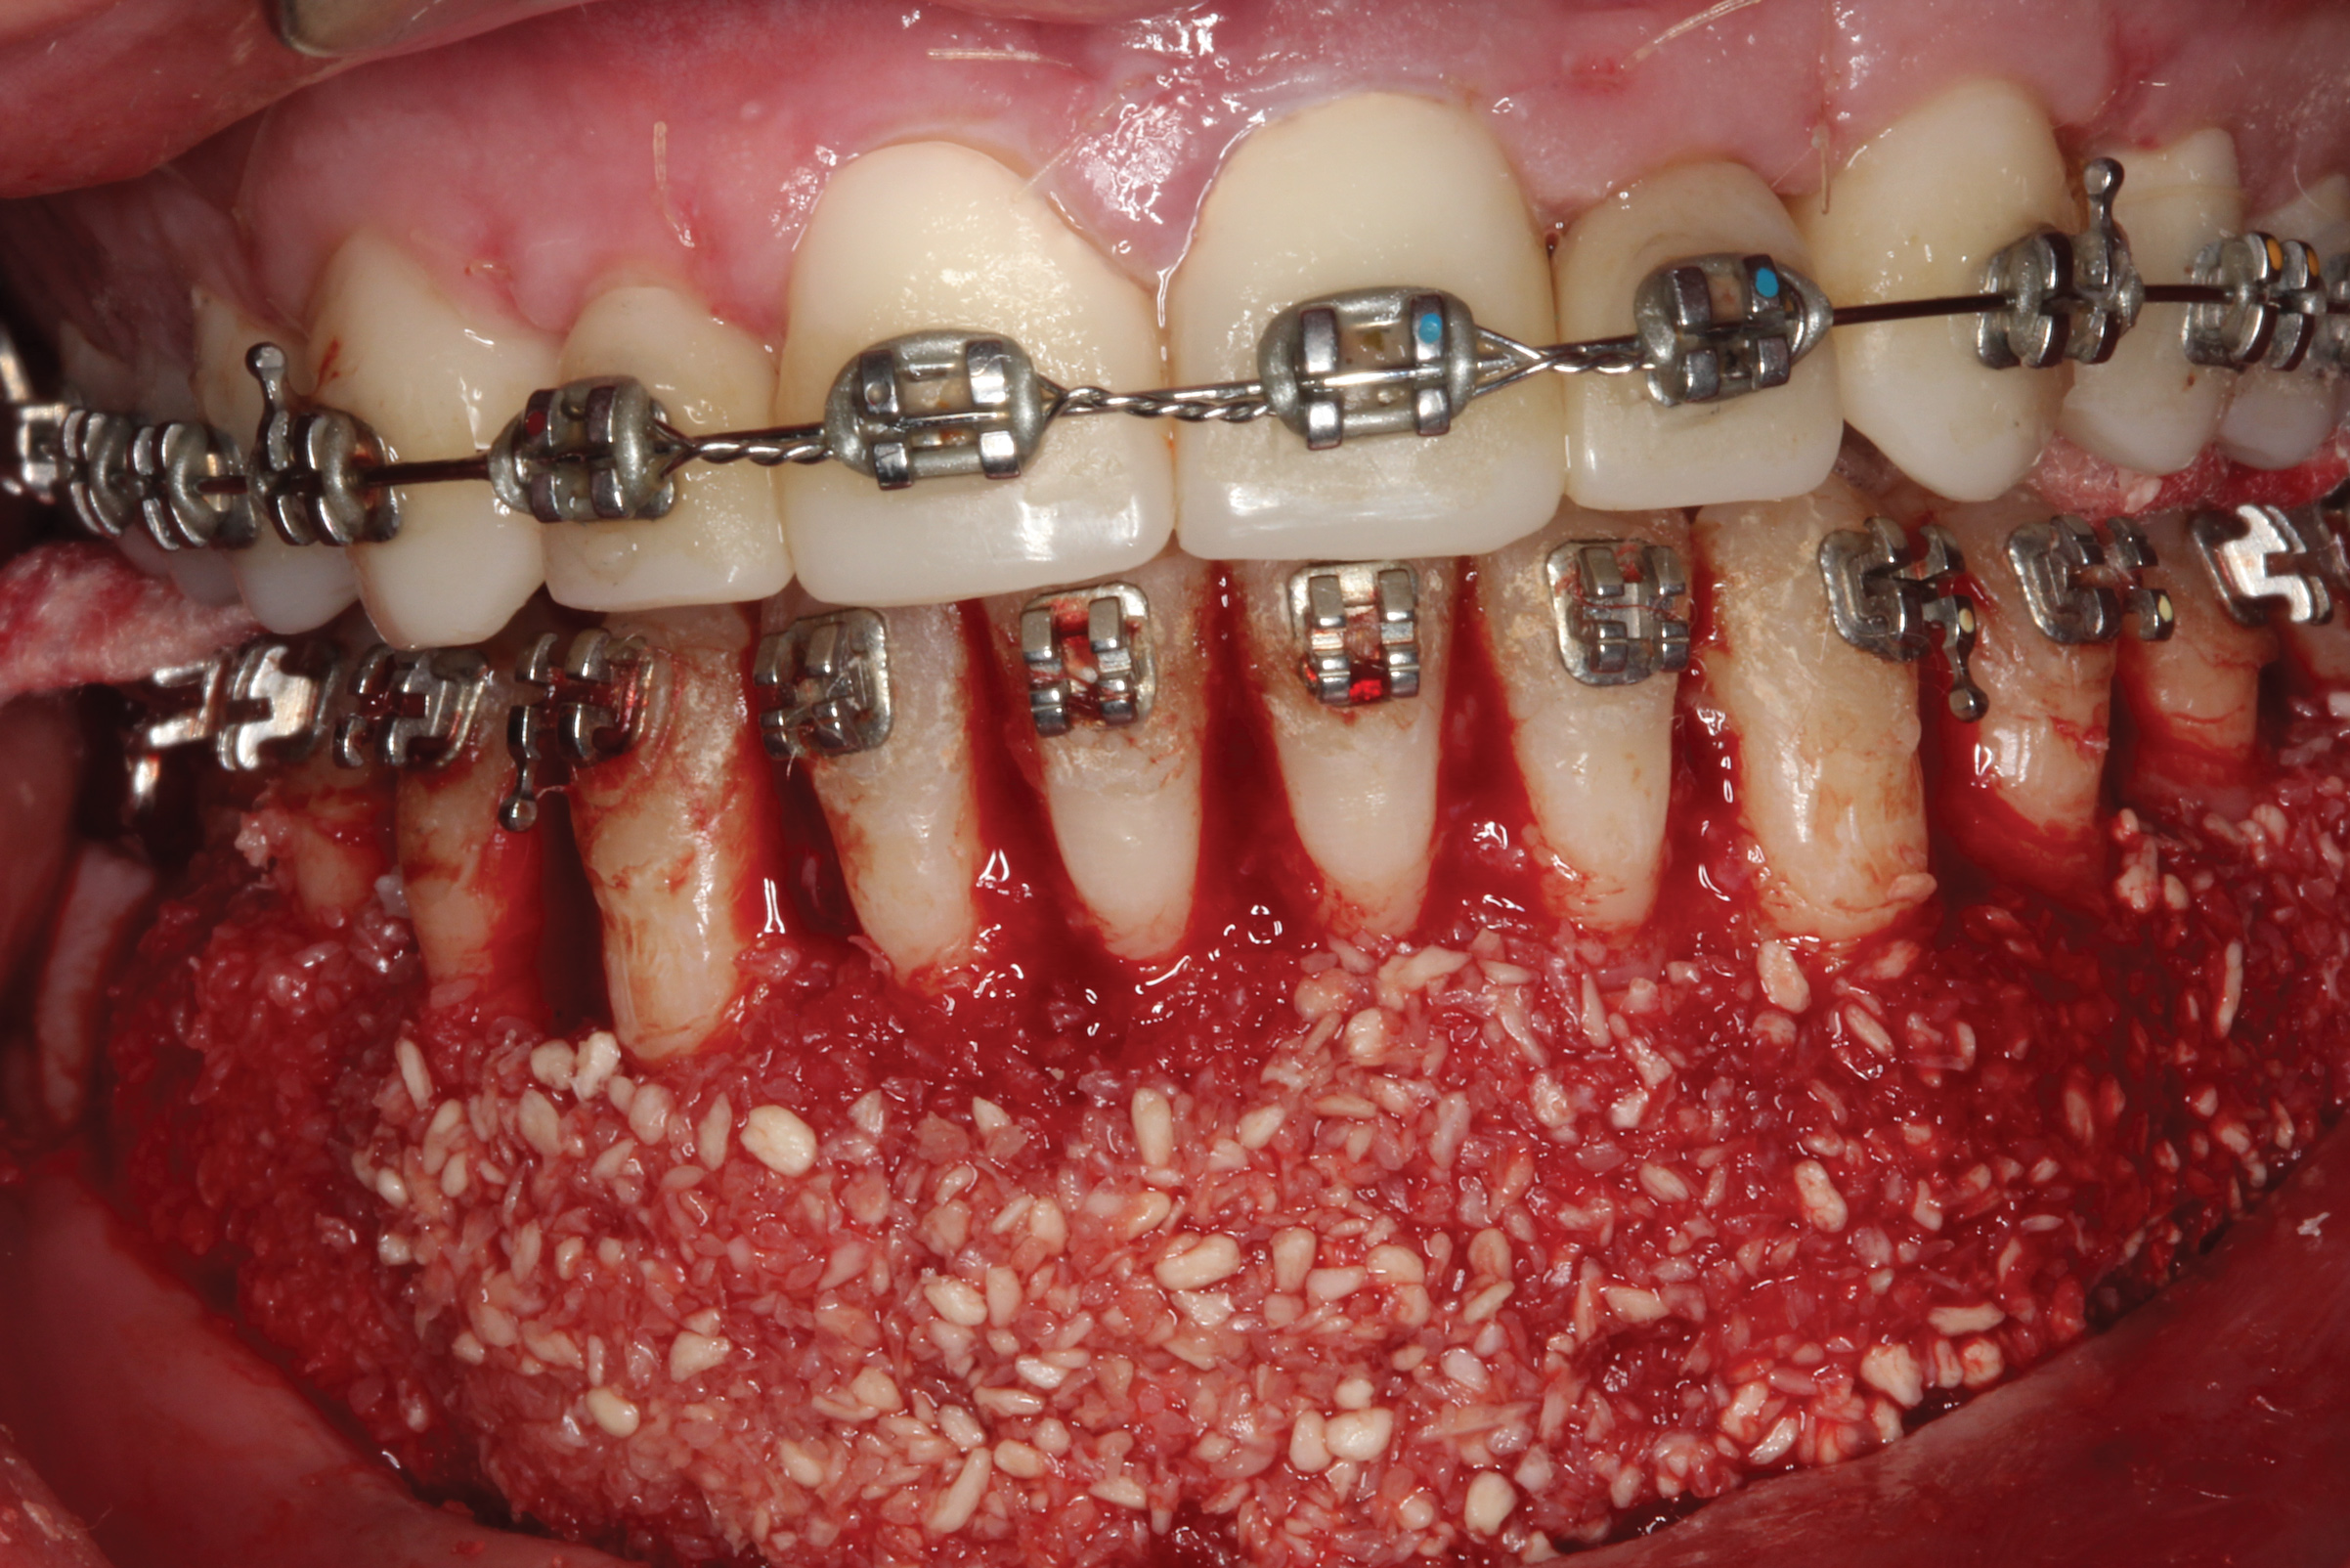

Fig 9. Corticotomies and dentoalveolar decortication of the mandibular anterior.

Figure 9

Fig 10. Corticocancellous particulate allograft positioned in the mandible to increase the orthodontic boundary conditions and provide an expanded envelope to reposition teeth.

Figure 10